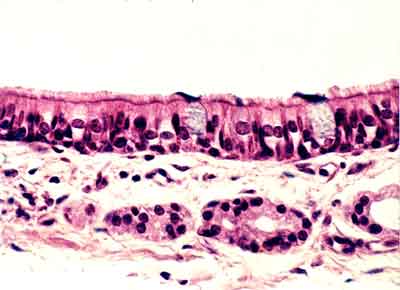

I-2 Mucosa nasal (Hematoxilina-eosina) |

Visión general: Fragmentos de cornete

nasal que permite observar en superficie un revestimiento epitelial con

aspecto de pluriestratificación, que asentando sobre un conjuntivo

con vasos y glándulas se denomina mucosa respiratoria y se mantiene

por un eje esqueletógeno en la porción media.

Visión específica: Al observar

el epitelio constatamos, a mayores aumentos, que la densidad celular y

por tanto nuclear varía en número y disposición.

En algunos campos aparecen con aspecto alargado los citoplasmas y los

núcleos en un único estrato, mientras que la forma mas habitual

de disposición es adoptando el patrón de pseudoestratificación.

Las células de reserva, triangulares y pequeñas, en los

niveles mas basales del epitelio presentan un núcleo redondeado,

las verdaderamente cilíndricas, mucho mas numerosas se encuentran

densamente dispuestas con lo que sus núcleos ovoides pueden situarse

tanto en los niveles intermedios como ocupando el citoplasma mas apical,

si bien el ultimo tercio del mismo no presenta núcleos sino las

diferenciaciones celulares que son en este tipo de epitelio dobles: las

células mas eosinófilas presentan un denso ribete de cilios

y las mas pálidas, con esta técnica, contienen secreción

de tipo mucoso.

Si estas células secretoras se presentan en pequeños grupos

las denominamos glándulas intraepiteliales, para diferenciarlas

de aquellas que observaremos en el conjuntivo, glándulas fundamentalmente

serosas. El eje de sostén es osteocartilaginoso.